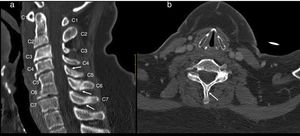

Spinal cordWith the corpse in the decubitus prone position with the cervical region in slight flexion and once the spinous processes had been marked, a midline incision was made. After separating the paravertebral muscles, the spinous processes and the cervical vertebrae laminae were accessed where the fractures of the spinous processes of C5, C6 and C7 were observed. After sectioning the vertebral laminae, the marrow was removed between C3 and D2 (Fig. 4a–c).

Images of the spinal cord trauma macroscopic study. In “a”, part of the spinal autopsy at the time of elevating the laminar webbing is shown. In “b” the webbing has been removed and the dorsal dura mater opened up to extract the complete cervical spinal cord, from the foramen magnum, along with the encephalon. No external injuries are identified on the spinal cord or spine additional to the fractures to the spinous processes. In “d” and “e”, corresponding to the specimen fixed in formalin, an intramedullary haemorrhagic focus C2–C3 (“d”) and C5–C6 (“e”) is identified, this last one more extensive and affecting anterior and posterior horns. In “e”, a softened intramedullary region is also identified, probably due to secondary injury.

Macroscopic studyAn intramedullary haemorrhagic infiltrate was observed at C3 level that in successive cuts extended up to C5 (Fig. 4d, e). The spinal cord looked normal below this level.